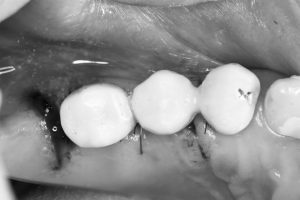

午後の方は、洞底皮質骨に絡み値も良く即時荷重非接触の仮歯まで装着しました。

(オペ後、仮歯装着まで)